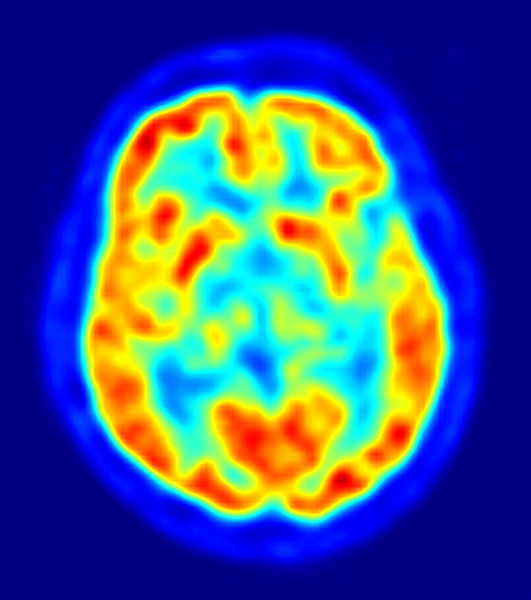

Probably the most controversial chapter in the whole book comes toward the end when Ropper bravely takes on the question, “When is somebody not dead yet?” Neurology is a field that can present a tangle of ethical and moral dilemmas. None more controversial it turns out than when defining when someone is actually dead. Ropper discusses how the need for a scientific definition of death became paramount when organ harvesting became possible. Conveniently, medical imaging of the brain and organ transplants came online side by side. Doctors could reasonably assess the likelihood that a brain would not recover. They called that brain death. Troubling though was that the body remained…alive. And bodies that donate organs remain alive, which can be morally problematic for some doctors. Imagine that. It bothers me too. Mostly, because I look at death not as an event but as a process. So choosing a moment of death has always sounded like pure hubris to me. Anyway, I was surprised that a doctor would cover this question and have hangups. Some of his colleagues clearly hadn’t thought about it at all.